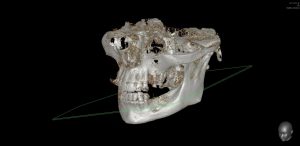

Теперь возьмём клинический случай (нижняя челюсть, отсутствия 35, 36, 37 зубов, атрофия альвеолярного гребня по ширине):

и рассмотрим его через парадигму методологического редукционизма. Или, если хотите, сквозь Бритву Оккама.

Мы имеем относительно небольшой дефект, не позволяющий, однако, установить имплантаты правильного размера в правильное положение. И два варианта остеопластической операции, НКР и АТККФ.